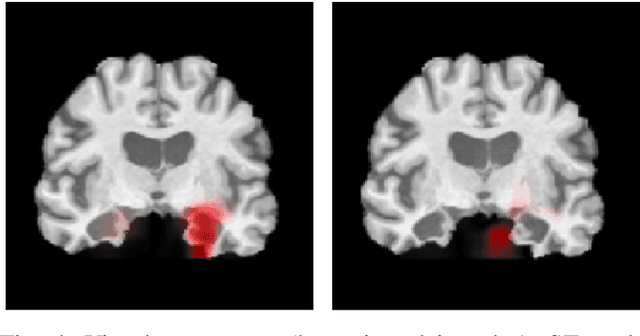

Abstract:Deep Convolutional Neural Networks (CNNs) are becoming prominent models for semi-automated diagnosis of Alzheimer's Disease (AD) using brain Magnetic Resonance Imaging (MRI). Although being highly accurate, deep CNN models lack transparency and interpretability, precluding adequate clinical reasoning and not complying with most current regulatory demands. One popular choice for explaining deep image models is occluding regions of the image to isolate their influence on the prediction. However, existing methods for occluding patches of brain scans generate images outside the distribution to which the model was trained for, thus leading to unreliable explanations. In this paper, we propose an alternative explanation method that is specifically designed for the brain scan task. Our method, which we refer to as Swap Test, produces heatmaps that depict the areas of the brain that are most indicative of AD, providing interpretability for the model's decisions in a format understandable to clinicians. Experimental results using an axiomatic evaluation show that the proposed method is more suitable for explaining the diagnosis of AD using MRI while the opposite trend was observed when using a typical occlusion test. Therefore, we believe our method may address the inherent black-box nature of deep neural networks that are capable of diagnosing AD.